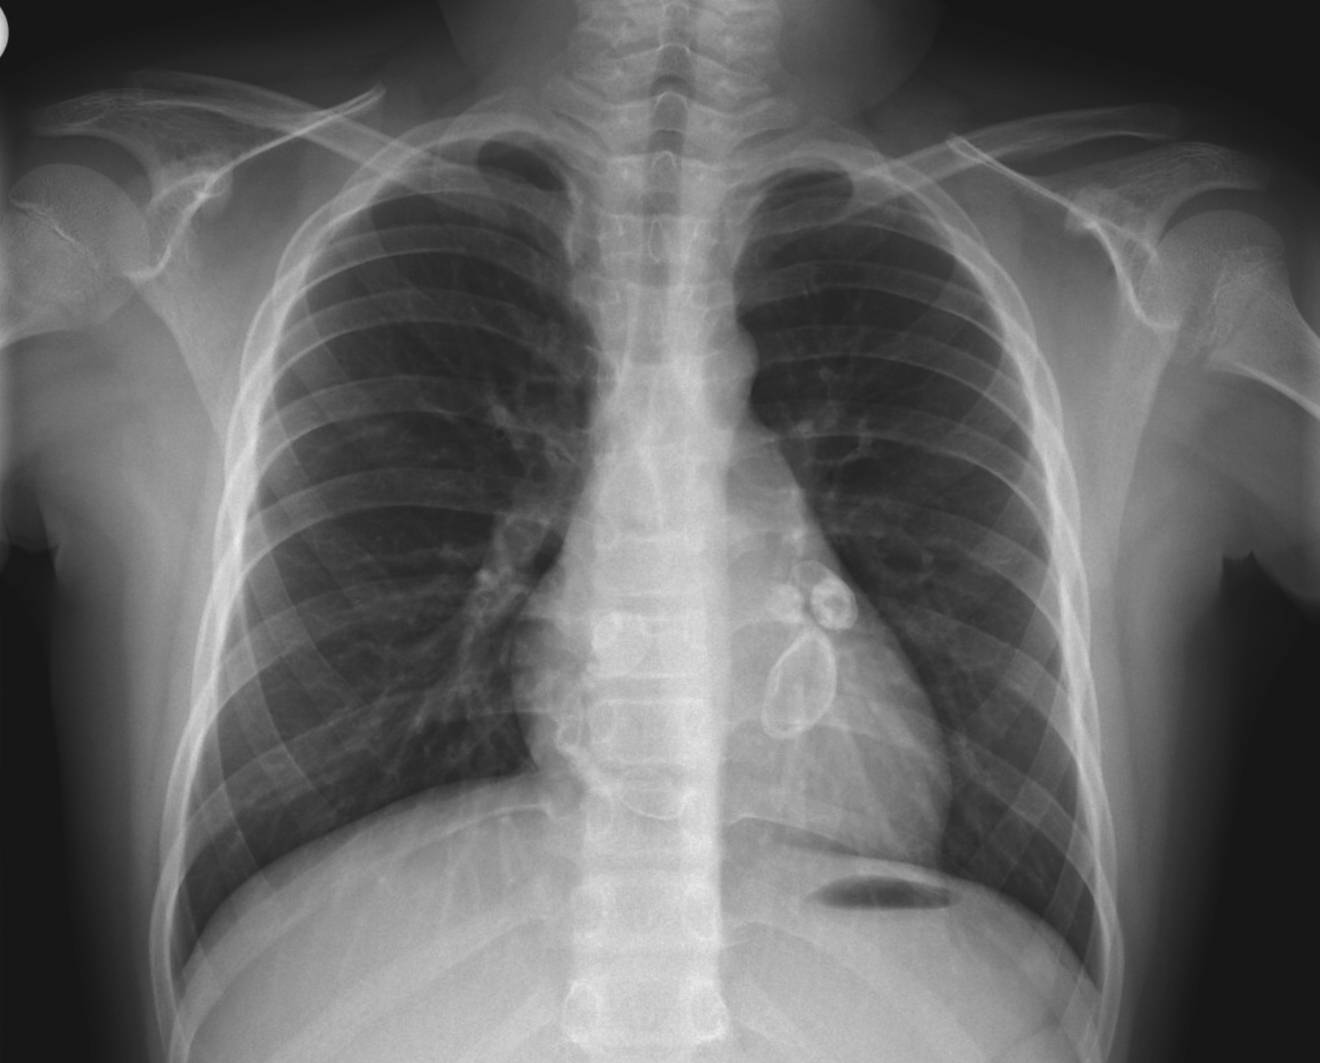

인체 내에서 중간 정도 크기의 동맥에 염증이 발생할 수 있으며, 그 중 심장근육에 혈액을 공급하는 관상동맥에 영향을 끼칠 수 있으므로 관상동맥의 확장이 있는지 심장초음파를 통해 확인한다.

- 심장 초음파 검사: 미세한 관상 동맥 변화나 동맥류를 확인한다.

- 혈관 조영술: 과거 관상 동맥 동맥류 진단에 사용되었으나, 현재는 심장 초음파 검사로 대체되는 추세이다.

관상동맥 병변이 잘 생기는 발병 10일째에 심장 초음파 검사를 실시하고, 이상이 없으면 발병 후 6주에 다시 검사한다. 관상동맥 병변이 없으면, 그 시점에서 아스피린 복용을 중단한다. 5일 이상 발열이 지속되는 것이 진단 기준 중 하나이지만, 다른 진단 항목에서 가와사키병이 명확히 의심되는 경우에는 5일이 되기 전이라도 치료를 시작해야 한다. 늦어도 발병 7일 이내에 치료를 시작하는 것이 좋다.